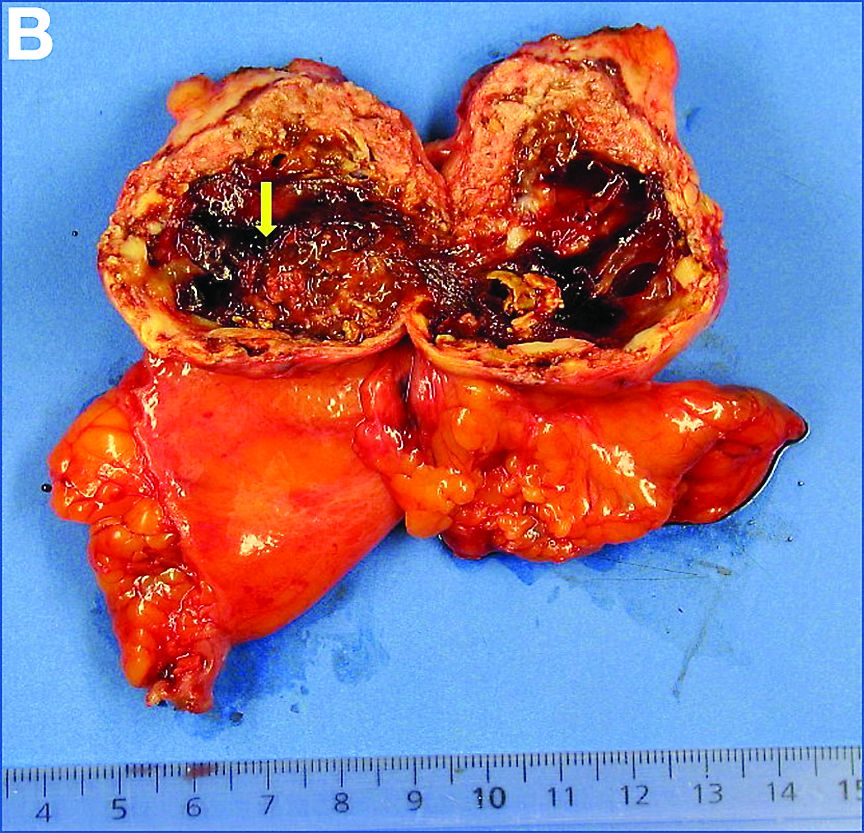

A 68-year-old woman, asymptomatic, with no medical history, underwent an abdominal computed tomography scan in a traumatic context. An enhanced series (Figure A) revealed a 4-cm cystic mass with tissue and calcified rim components located under the left liver (Figure A, arrow) inside the ligamentum teres. The lesion was supplied by a left hepatic artery branch. The frontal view showed the mass drainage into the left external iliac vein through a long pedicle (the umbilicus vein connected to the left inferior epigastric vein) (v).

A laparoscopic resection of this mass was performed because of the risk of spontaneous hemorrhage linked to the dense tumoral vasculature and the lack of formal histologic diagnosis. During the procedure, the surgeon observed a cystic mass attached to the ligamentum teres between the liver and the umbilicus. At pathologic examination (Figure B), a well-circumscribed largely cystic mass, with a fibrous and calcified shell and hemorrhagic modifications (arrow) was observed.